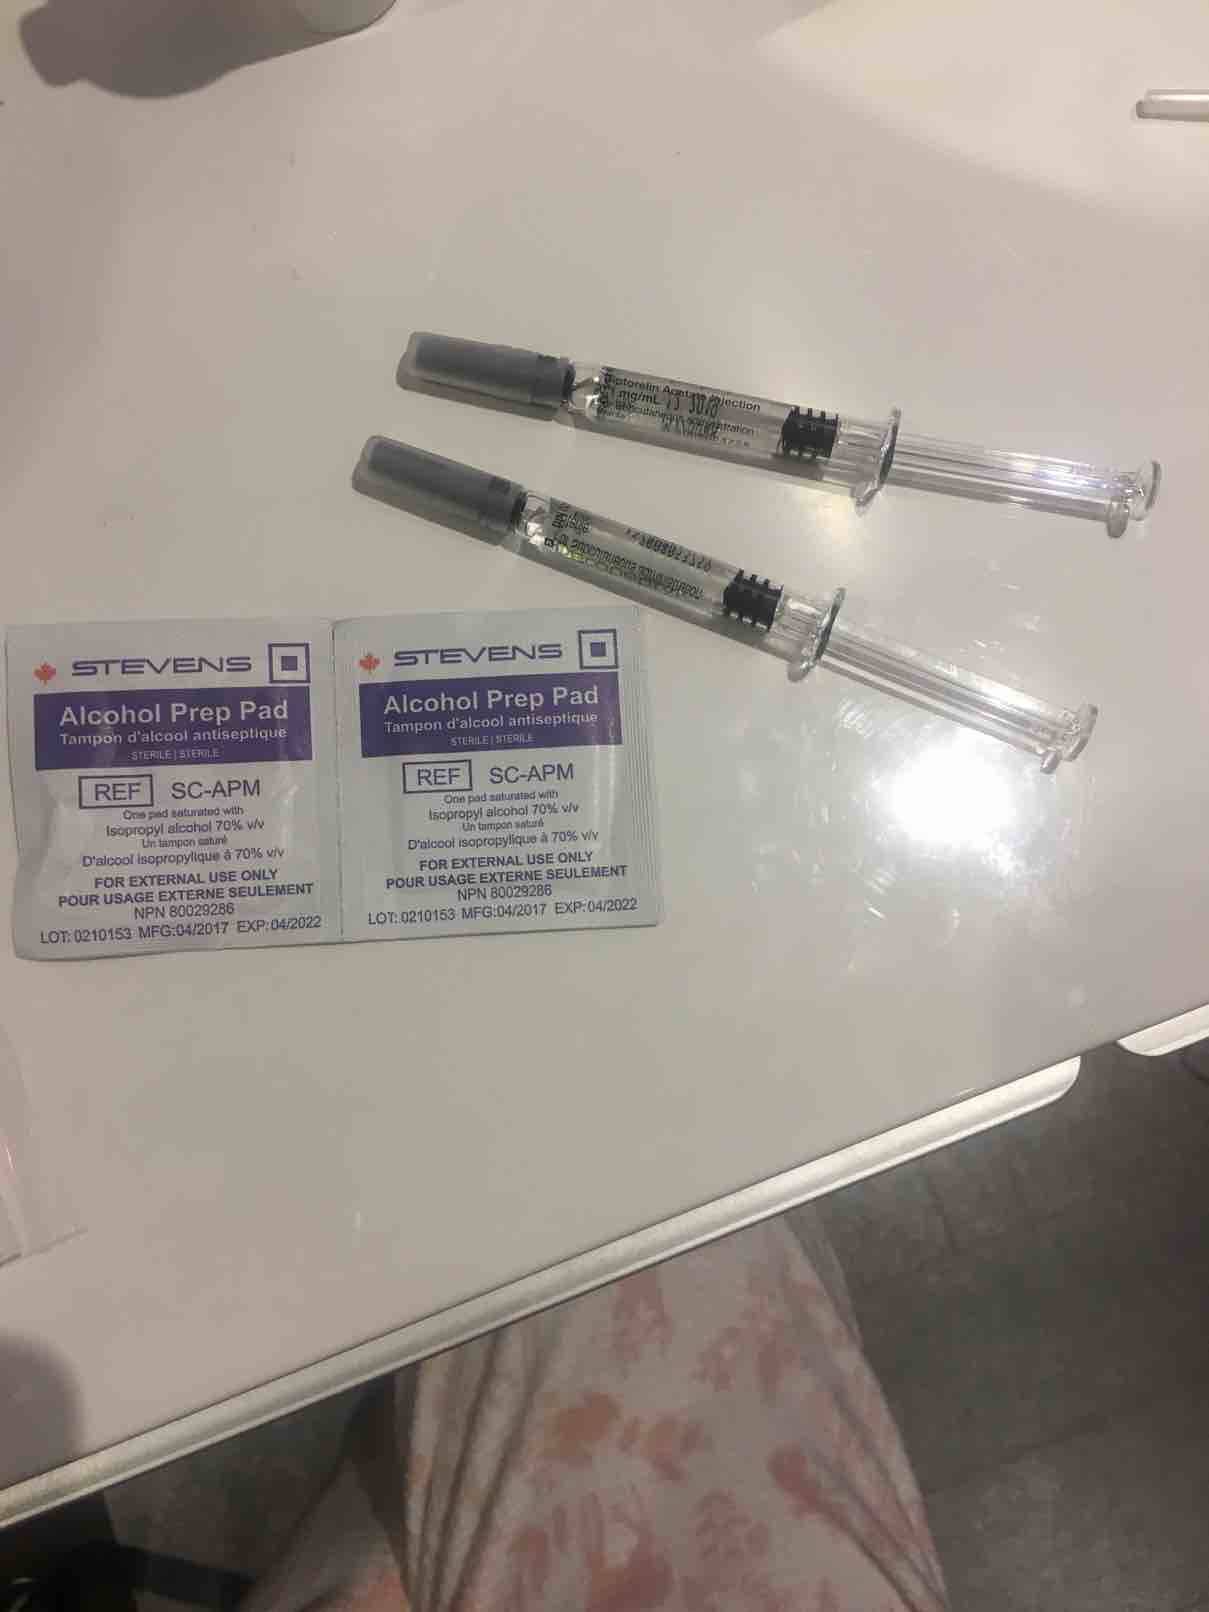

本人女29未婚未育手术前偶尔知道可以冷冻卵子 前提是要在化疗前做大家都知道化疗药物复合卵巢子宫都有一定副作用。一般医生都是建议内分泌药吃五年才可以考虑生孩子 生完继续内分泌五年我自己认为越年轻卵子质量也越好 数量可能也会相对高一点当我五年后34岁 我的卵子还是29岁的状态 而且是未受化疗药物污染的。我觉得为什么不尝试呢以下就来亲说我的取卵过程第一次去咨询的时候做了阴超显示可能有15颗左右卵子第二次是月经来的第二天 又检测了一下卵子 查了血接着自己回家打menopur 75IU ➕ purogan 225IU 每天还要吃一颗来曲挫到第五天的时候去诊所验血 下午通知加打一针orgalutran 接下来的10天左右都是每天定点自己在肚子上打三针 最后五天开始每天检测卵泡大小是否超过17mm到了周一终于不用再打针了 因为周二可以取卵了我没有做全麻 首先做椅子上吃了止痛药 放松的药 还有打了头孢。时间差不多就走去手术室 准备手术术前医生先帮忙清洗下体感觉跟生孩子差不多的姿势 也不知道他弄了些什么 不痛 就是这时候开始打麻药了 有点晕接着正式开始手术 就看到屏幕里一根针插入卵泡把它慢慢吸走 接着换另一个卵泡接着吸一共吸了十分钟 就被告知手术结束了腿上轮椅回到休息室休息了一个小时 并且打了点滴 才让我不那么晕也不想吐了 回家接到电话 取出22枚卵子。成熟的可以冷冻的有9颗好吧虽然一残都没到。但我多了一条后路哪天想生孩子 至少我还有年轻且健康的卵子存在想想心里也舒服点不是么附上我这两周自己给自己打的针 还有最后那些黑黑的球球就是卵泡😁